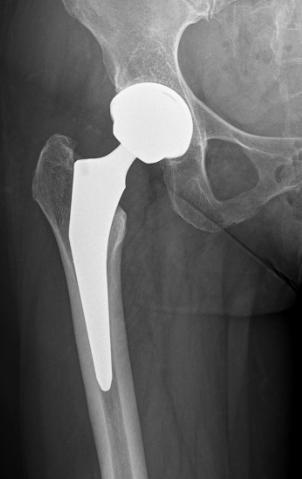

Minimal invasive Hüftgelenkersatz